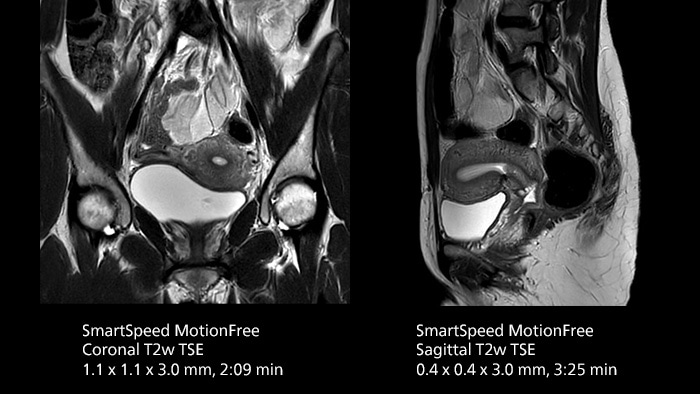

After using Philips SENSE, Mermaid Beach had adopted Compressed SENSE that offers a k-space sampling approach to speed scans while preserving details. “And now SmartSpeed enables denoising the sparse under-sampling in a new way that has allowed us to increase acceleration and bring image quality to a whole new level,” notes Kennedy, “It’s truly revolutionized our MRI work space, especially for difficult patients.”

Philips SmartSpeed has multiple approaches to denoising. Raw k-space data, coil sensitivity and coarse background information are all used and reconstructed with artificial intelligence (AI) to provide true resolution in shorter scan times1 with more sequences. Kennedy states, “I noticed that since the introduction of SmartSpeed, our day is a lot less stressed. When complicated exams need extra time, we just get on with them. And if we need to do something new or extra, we have the time for it and our workflow is still a lot more efficient.”

The broad applicability of SmartSpeed allowed the imaging center to use this technology across many scan types, including non-cartesian imaging as used for motion correction in uncooperative patients or challenging anatomies.

“We use SmartSpeed frequently on difficult areas such as the abdomen and chest where it is common to see respiratory motion and other bowel motion,” says Kennedy. In MSK scans they use SmartSpeed not only for speeding up their exams, but also to reduce slice thickness and improve resolution “We may be increasing the number of slices, but we’re still doing this in less time than we were previously.”